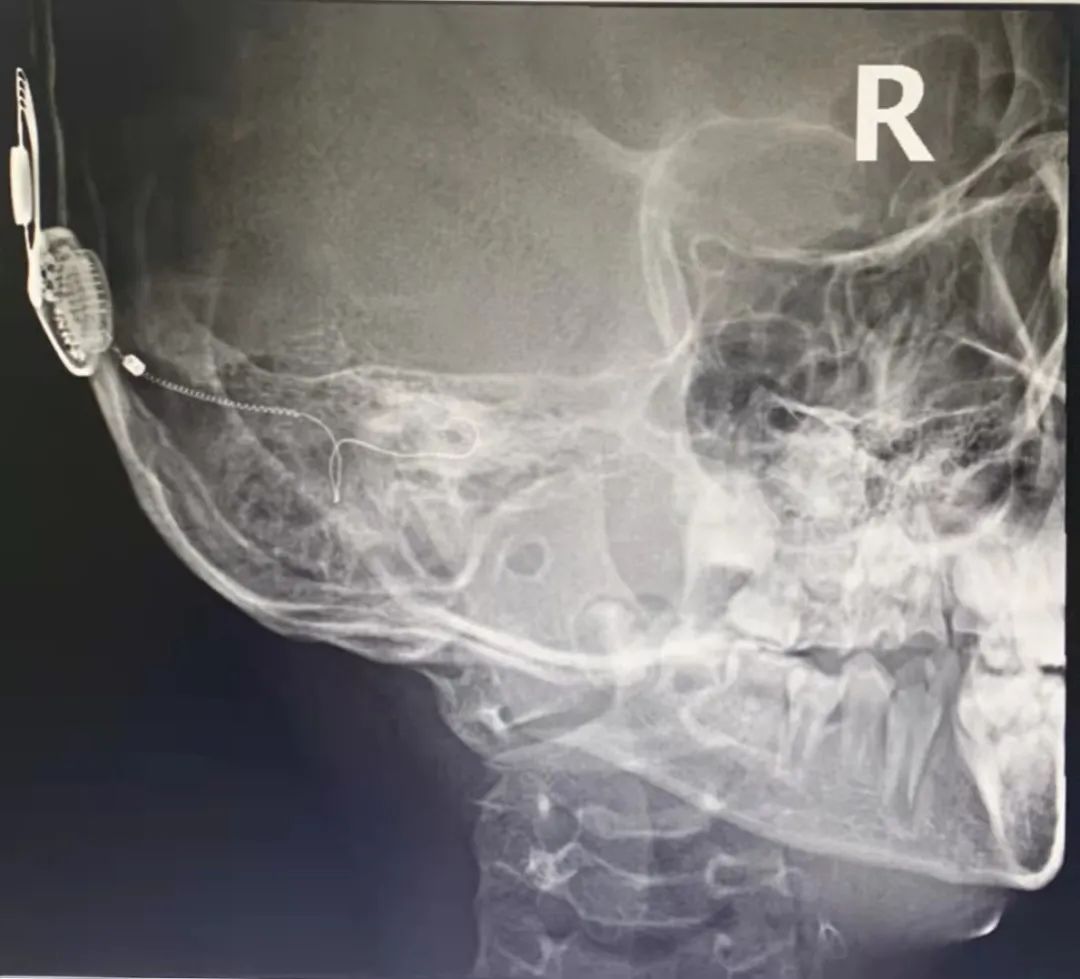

术后为轩轩行头颅 X 片,见人工耳蜗电极漂亮地循着耳蜗的「轨迹」绕圈,表示着人工耳蜗电极成功植入。